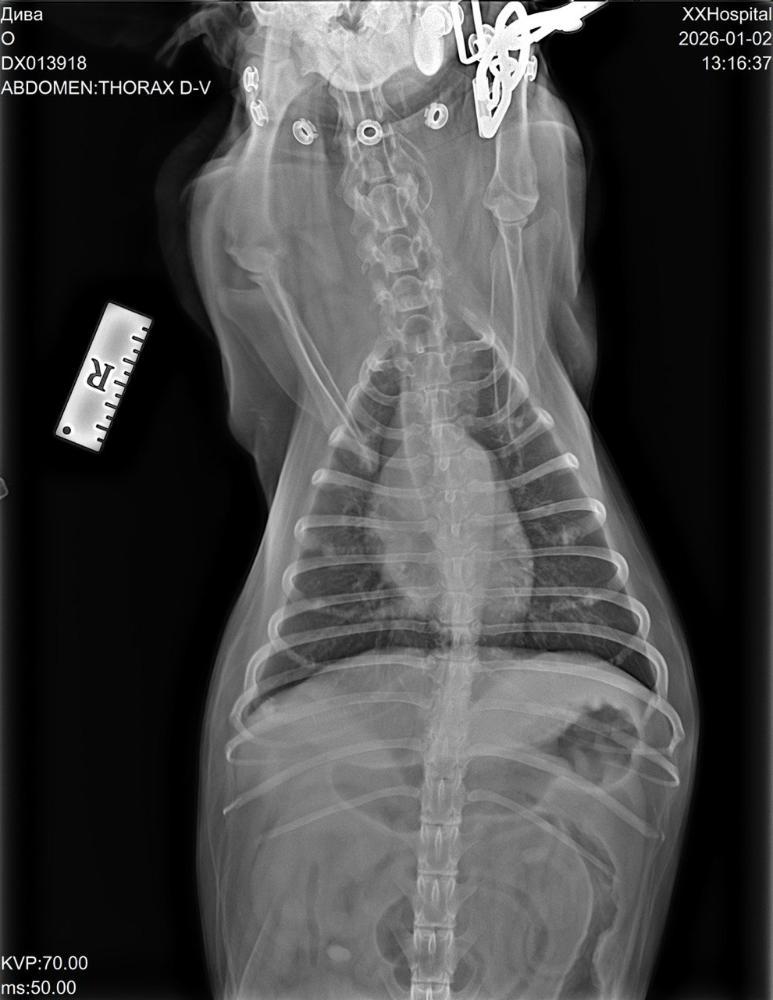

С'ездили мы сегодня к врачу, сделали кардио обследование, рентген, дополнительный анализ ( ждём всё на почту).

По сердцу всё в пределах возраста, сделали рентген - затемнение в лёгких, сдали дополнительные анализы ( по результатам либо надо будет делать КТ, либо бронхоскопию).

Кардиолог, рентген, анализы - 9339р.

Зоотакси -1330р.

Остаток: минус 6519р.